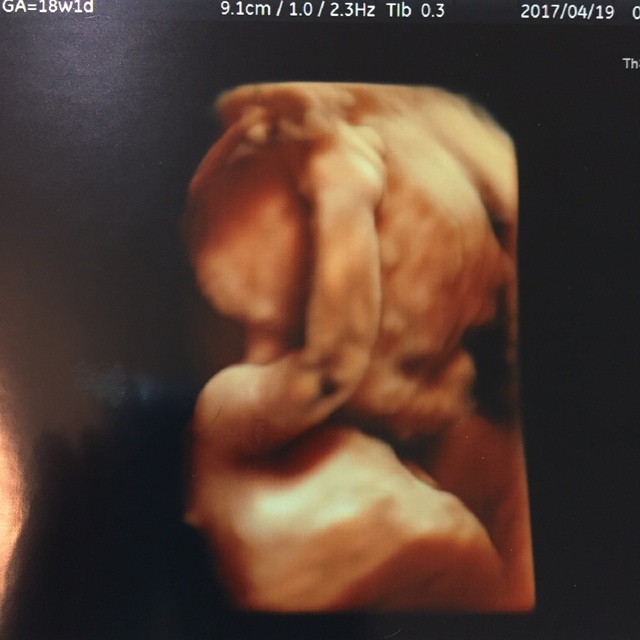

18週5日(18w5d・女の子)|ゆきち56 さん(37歳)

エコー写真撮影時のエピソード:

3Dエコーで、初めて顔を見せてくれたと思ったら、笑っているような表情だったので、思わずエコーを受けながら笑ってしまったので、気に入っています。それまでのエコー写真を見てもそんなに大きな反応がなかったパパも、この写真を見た途端に笑っていました。

18週の頃はやっと悪阻が落ち着いてきて、食事が取れるようになり、妊娠したことを素直に喜び、栄養配分に気を付けて食事内容やカロリーを考えながら生活するようになりました。